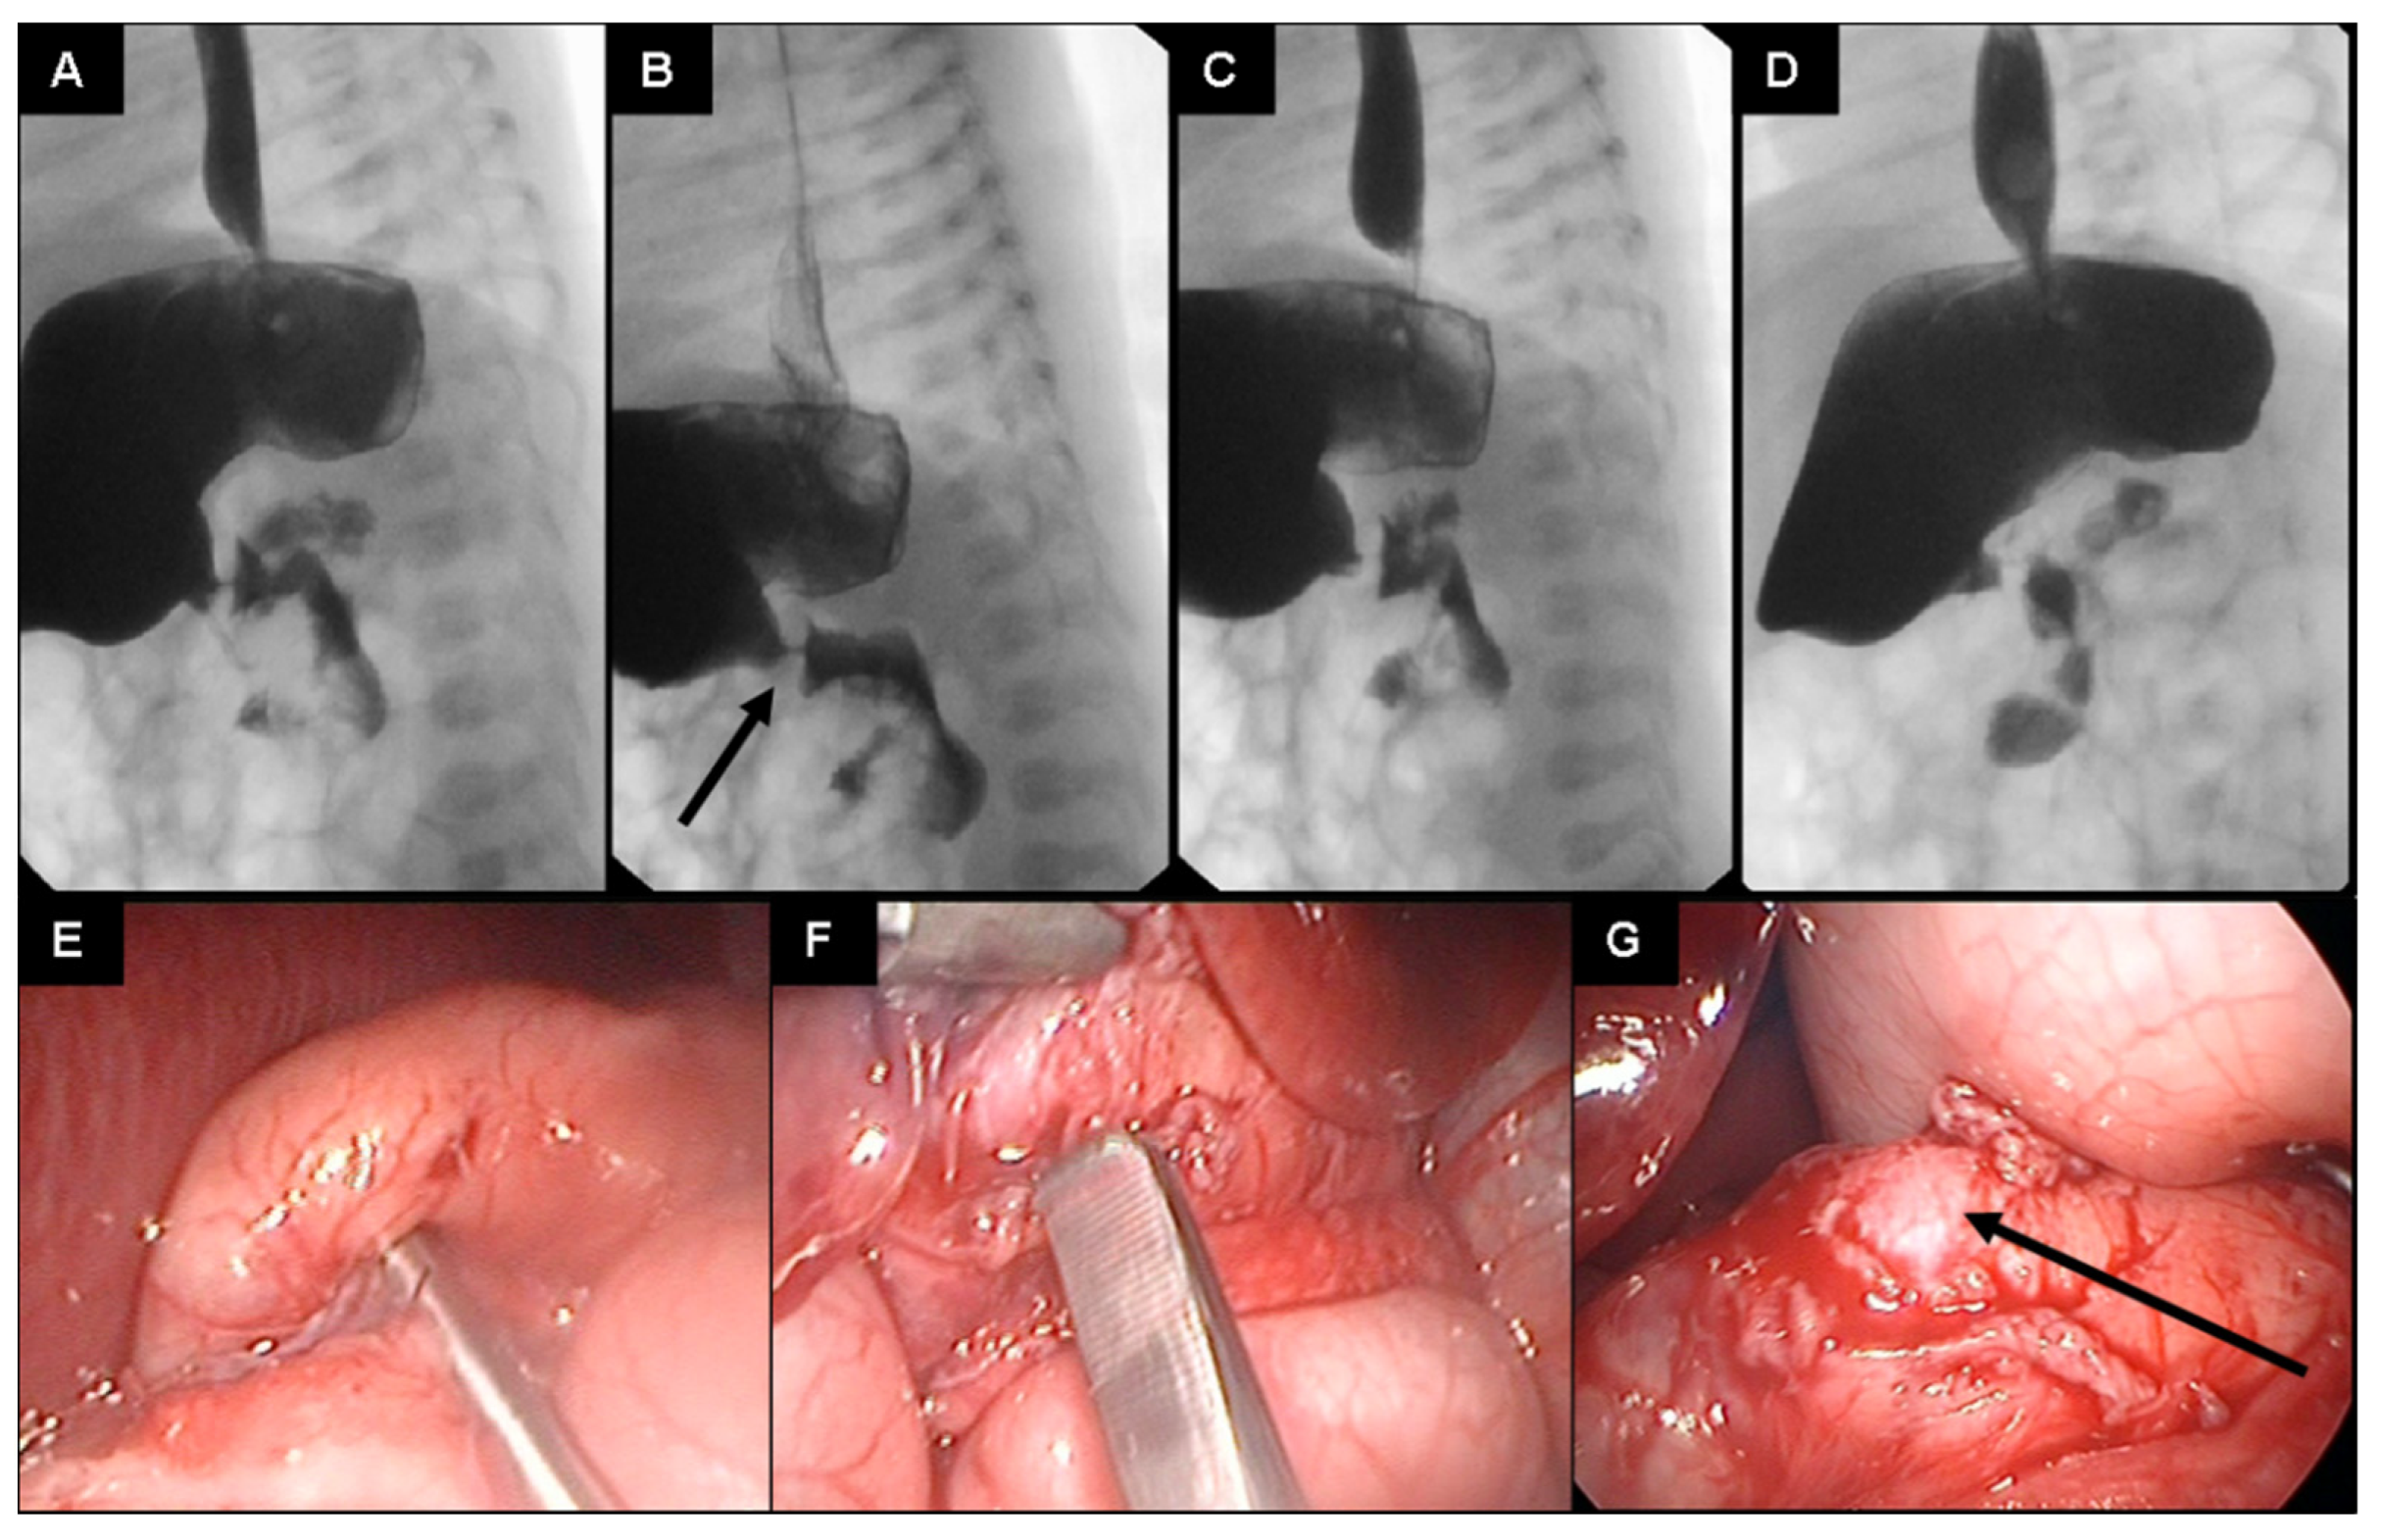

DBMCI Egurukul - ❓Upper GI series demonstrating a narrow and elongated pylorus with a narrow lumen (“string sign”), appearing as puckering of the mucosa (“double track sign”) is a feature of❓ A. The Gastrointestinal String Sign | Radiology Hypertrophic pyloric stenosis- “string sign” | Pediatric surgery, Pediatrics, Radiology Peds in a Pod on X: "If you've listened to Poopcast 3.0, check out this image of the “String sign” for pyloric stenosis. This is a the finding from an UGI, which Hypertrophic pyloric stenosis. ( ) A diagrammatic representation of the... | Download Scientific Diagram Pyloric Stenosis String Sign